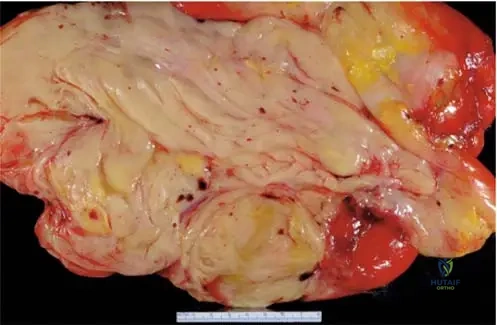

A 15-year-old female presents with a painful mass in her distal femur. A gross specimen of the resected tumor is shown. What is the primary characteristic that defines this tumor as an osteosarcoma?

Correct Answer: B

Rationale: Regardless of the gross appearance, the fundamental pathological definition of osteosarcoma is a malignant bone-forming tumor, meaning malignant cells producing osteoid. While gross specimens can show variability (e.g., blood-filled spaces in telangiectatic variants), the microscopic production of osteoid is the diagnostic hallmark. The image shows a destructive, heterogeneous mass consistent with a malignant bone tumor.